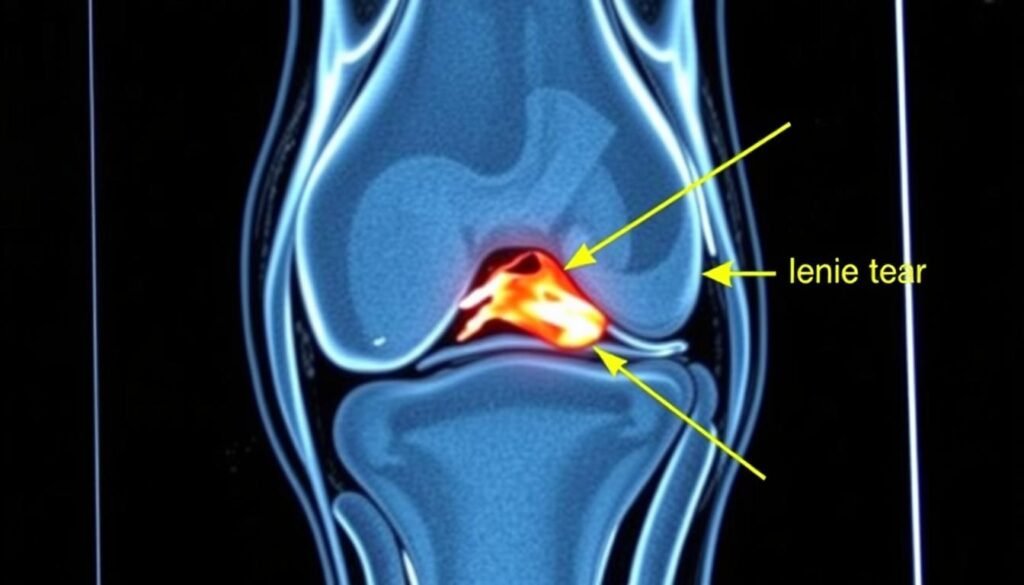

MRT-Bild eines Meniskusrisses im Kniegelenk

MRT-Aufnahme eines Kniegelenks mit deutlich erkennbarem Meniskusriss (Pfeil).